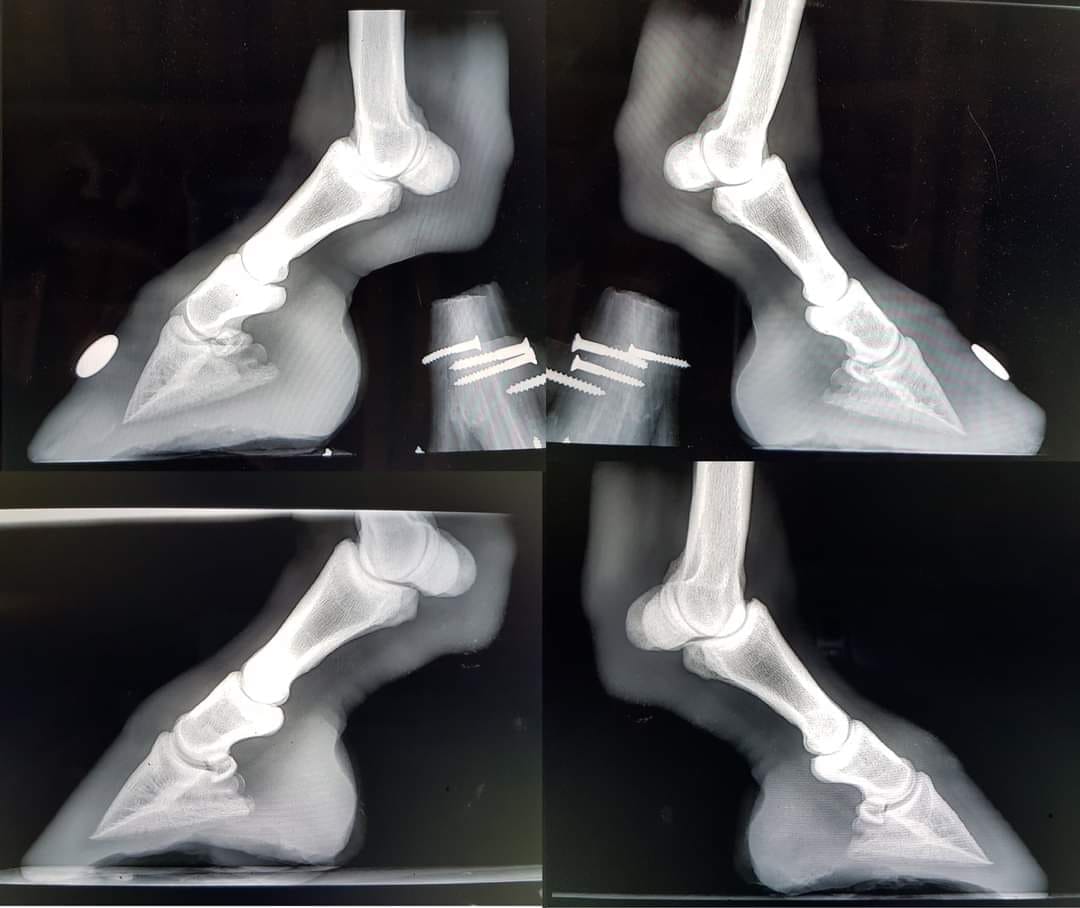

Les radios de Tristam au début de sa réhabilitation et un an plus tard.

Sur cette photo, bien que le pied ait récupéré un joli aspect, il n'est pas encore totalement guéri.

Le postérieur droit de Tristam 5 ans après le SME et la fourbure.

Grâce à une gestion adaptée, il n'a conservé aucune séquelle sur ce pied qui était pourtant le plus atteint. Il n'a jamais refait de crise et, bien qu'il ait été trop gros au moment de ces clichés, ses pieds sont restés parfaitement normaux et sains. A titre de comparaison, les photos suivantes ont été prises avant et en cours de réhabilitation :